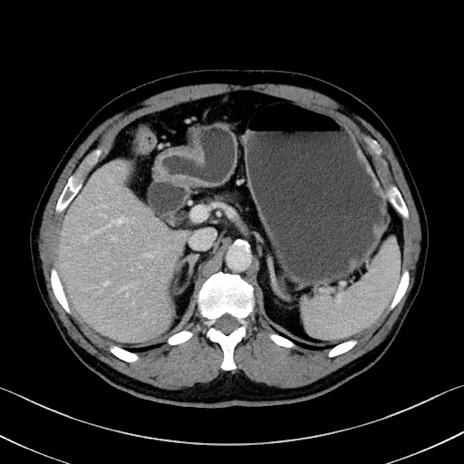

冠状断像

【症例】70歳代 男性

【主訴】腹部膨満、嘔吐

【現病歴】昨日より腹部膨満感出現。本日増悪し、仙痛出現。嘔吐あり、受診。

【既往歴】糖尿病、胆摘後

【身体所見】BP 149/80mmHg、HR 74/min、BT 35.9℃、腹部:膨満、軟、圧痛なし。腸雑音減弱あり。上腹部正中切開瘢痕あり。

【データ】WBC 13500、CRP 1.72